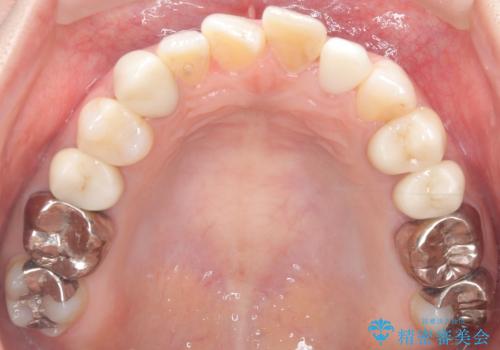

【セラミッククラウン】歯の根元が欠けた、歯が揺れている気がする

- 主訴:上の前歯の根元部分が欠けた、欠けた歯たまに揺れている気がする。

過去にも同じように欠けて、通っている歯科医院で応急処置してもらったが、また欠けてしまった。

左上2番の唇側歯頚部が欠けており、根管治療を受けている歯でした。

レントゲン写真撮影を行ったところ、歯の中の土台が外れ欠けている状態でしたので土台と被せものの治療を行うこととしました。

外れ欠けている土台をまずやり替えた後、根管治療後の緊密な封鎖を目的としオールセラミッククラウンをセットしました。